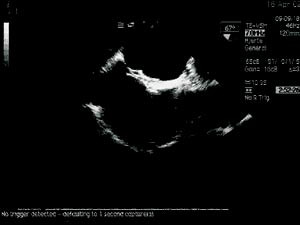

Transøsofageal ekkokardiografi ble utført med pasienten i venstre sideleie og lett sedert. Atrieseptum sees vanligvis best fra en midtøsofageal firekammer- eller langakseposisjon (22). Saltvannskontrast bestående av 8 ml saltvann med 2 ml oppslemmet luft ble satt i en vene på høyre arm. Man registrerte så eventuell overgang av mikrobobler fra høyre til venstre forkammer (23). Kontrasttesten ble utført uten og med Valsalvas manøver.